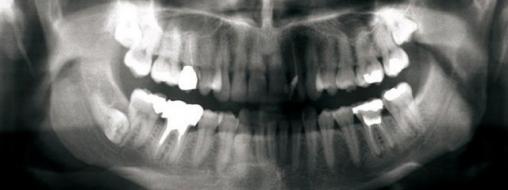

Guy Princ, La Revue du Praticien Panoramique dentaire. Les dents 15-22-46-36 ont fait l’objet de traitements endodontiques. Panoramique montrant les inclusions des dents de sagesse 18, 28 et 48. La dent de sagesse 48 est incluse horizontalement.